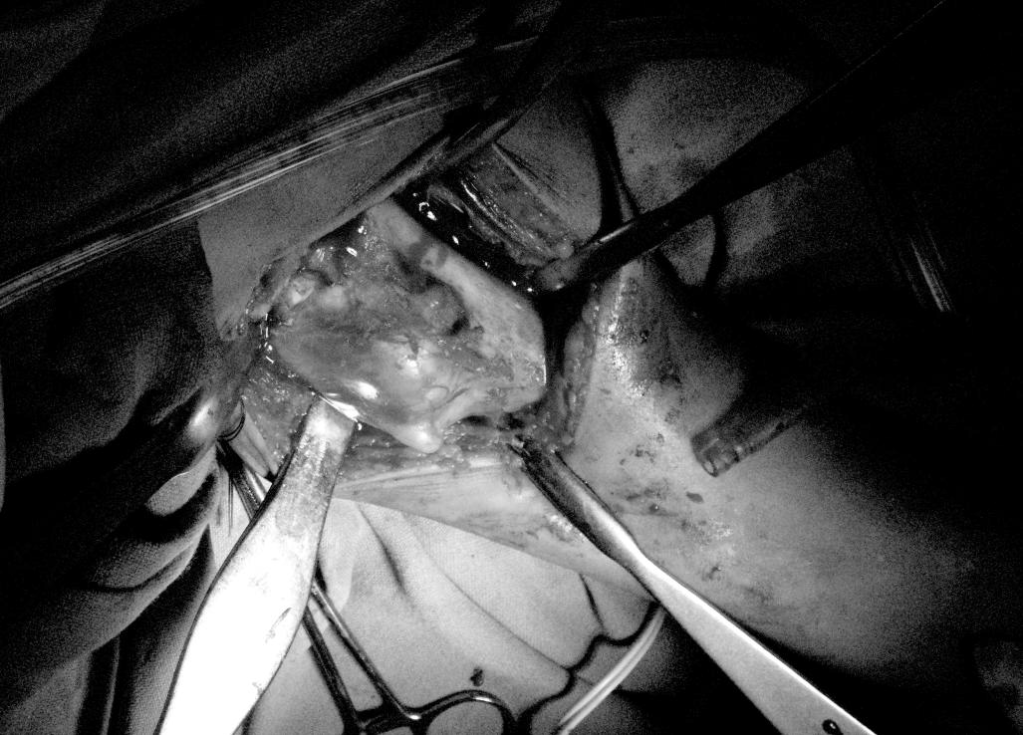

Per operative

The biopsy confirmed the diagnosis

BEFORE REMOVAL